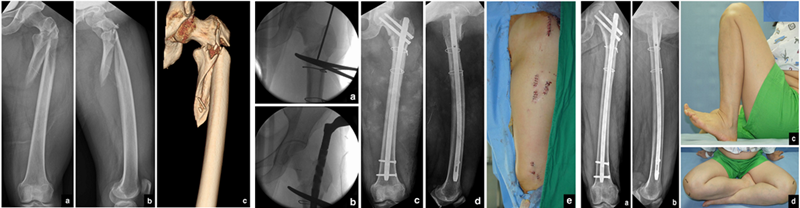

肖XX,男,35岁

术后

术后1年